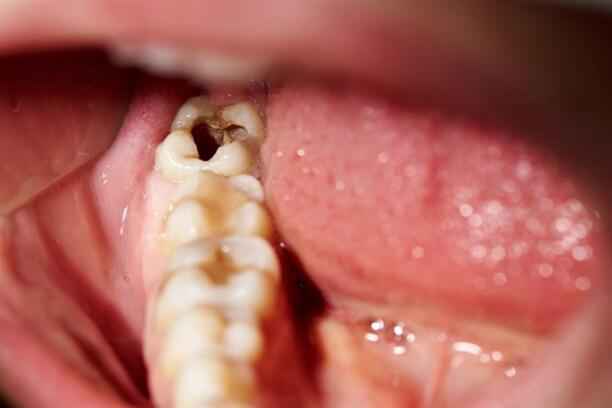

أعراض تسوس ضرس العقل:

يُعد تسوس ضرس العقل من المشكلات الشائعة نظرًا لصعوبة تنظيفه وموقعه الخلفي، وتظهر أعراضه بشكل تدريجي ومتفاوت، ومن أبرزها:

• ألم خفيف يتحول تدريجيًا إلى وجع حاد عند تناول السكريات أو المشروبات الساخنة.

• حساسية مفرطة عند ملامسة الضرس أو الضغط عليه أثناء المضغ.

• ظهور بقع داكنة أو تجاويف واضحة على سطح الضرس.

• رائحة فم غير مستحبة ناتجة عن تراكم البكتيريا وبقايا الطعام.

• التهاب اللثة المحيطة بالضرس مع نزيف بسيط أحيانًا.

• انتشار الألم إلى الأذن أو الفك السفلي في الحالات المتقدمة.

إهمال هذه الأعراض قد يؤدي إلى مضاعفات أكثر خطورة مثل الخراجات أو انتقال العدوى للأسنان المجاورة.